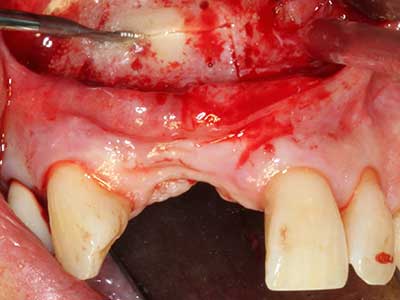

Indication: Bone splitting

Bone tissue is not simply a mineral structure but also contains a substantial proportion of collagen fibres. This means it not only has good compressive strength but also a degree of flexibility, which can be taken advantage of when performing bone augmentations. In the classical expansion procedure using bone splitting, the atrophied alveolar ridge is split longitudinally and carefully expanded after reaching an adequate osteotomy depth (Fig. 13-16), ideally without substantial removal of the periosteum (Brugnami, Caiazzo et al. 2014, Stricker, Fleiner et al. 2014). Screw and plate systems with increasing expansion distance have proven effective in separating the two bone lamellae while remaining below the fracture threshold. In general, residual bone widths of at least 3–4 mm are required (Chiapasco, Zaniboni et al. 2006) to guarantee adequate flexibility and sufficient bone coverage of the future implants. If necessary, a vertical relief osteotomy on one or both sides can improve flexibility. A combination with additional augmentation techniques, particularly on the buccal side, has been described as an alternative to the classical technique.

The splitting procedure is particularly atraumatic and there is no significant loss of dimension when using piezosaws, and there are no significant differences between implants in split jaws and implants in an alveolar ridge without a bone deficit (Chiapasco, Zaniboni et al. 2006, Danza, Guidi et al. 2009). However, sufficient continuous irrigation is essential, particularly with locally restricted and deep splitting to prevent thermal stress in the apical osteotomy regions.